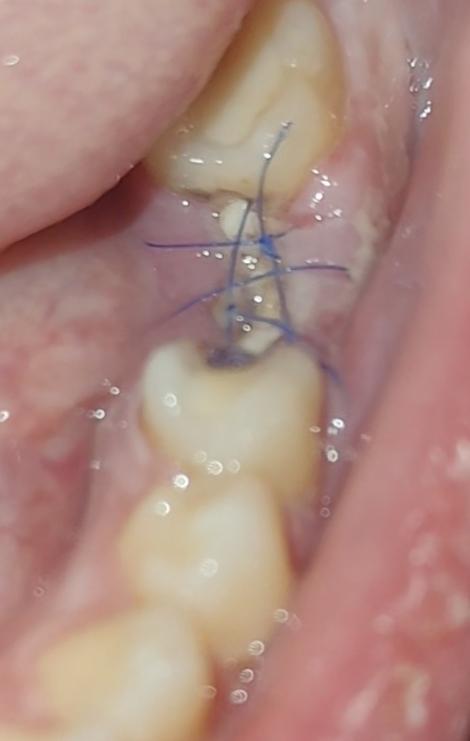

Здравствуйте . сегодня 6ой день после удаления зуба. Лунка выглядит так. Все ли нормально? Начитался про альвеолит... Страшно. Есть небольшая боль

1 ответ

нет!